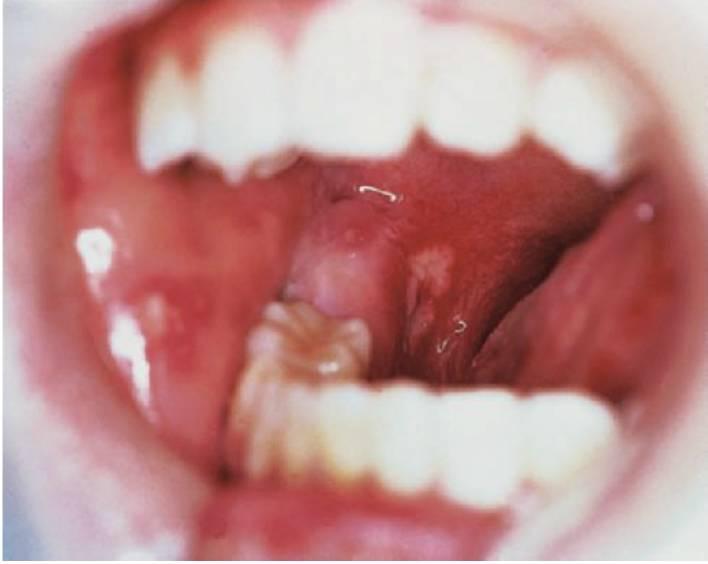

- Deficiencias de adhesión leucocitaria (fig. 10.4).

- Periodontitis prepuberal generalizada (fig. 10.4).